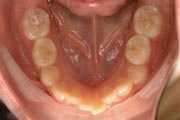

Crowding

Before